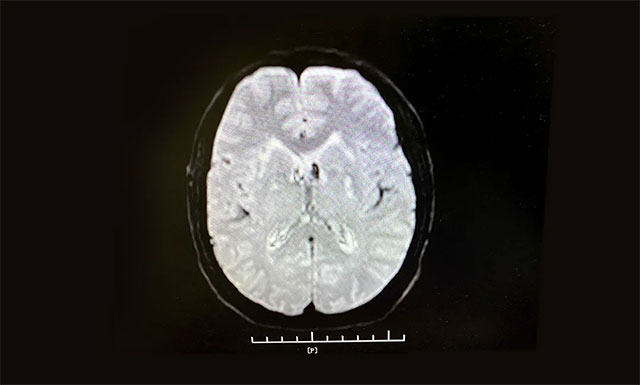

▲ 根据急诊CT影像结果,排除患者脑出血